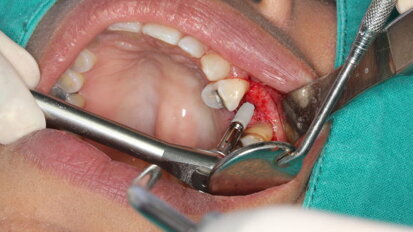

Avulsion in Paediatric Dentistry: Management of a Double Dental Emergency in a Child

General dental practitioners and paediatric dentists face real dental emergencies that effect children, especially dental trauma. Avulsion is considered, in...